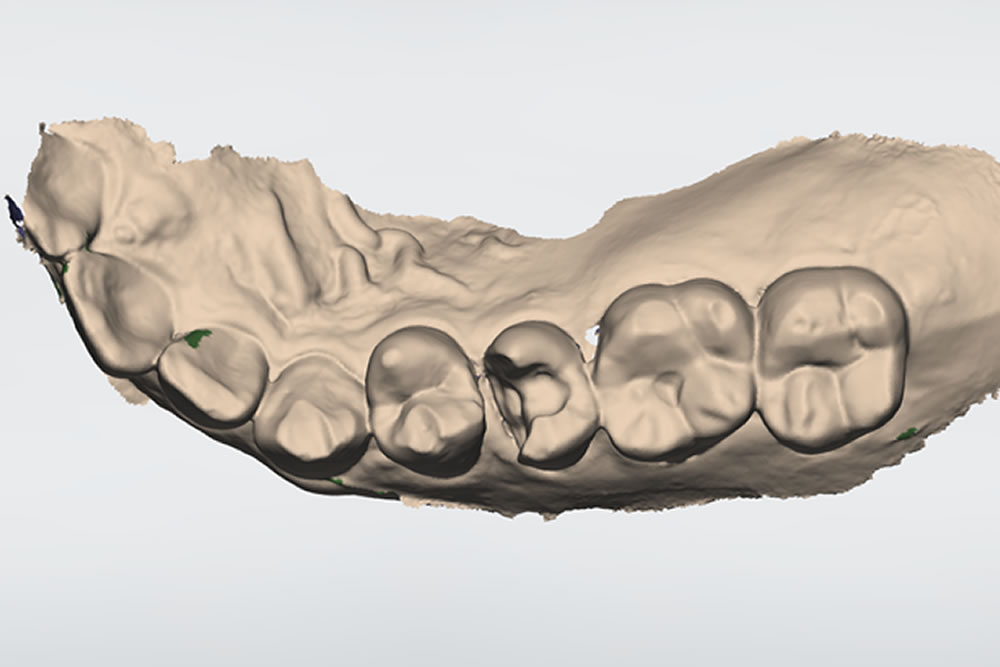

口腔内スキャナーによる歯型の採取

患者さまのお口に合ったつめ物・かぶせ物を製作するためには、精巧な歯型が必要不可欠です。当院では口腔内スキャナーを用いて精密な歯型のデータを採取しております。光をあてるだけで歯型を採取することができるため、嘔吐反射が強い方も快適な処置が可能です。

噛む面と右の側面から見るとこのようになっています。患者さまと相談した結果、こちらの銀歯を取り除き、白い歯(ジルコニアセラミック)を被せて見た目を改善する治療計画を立てました。